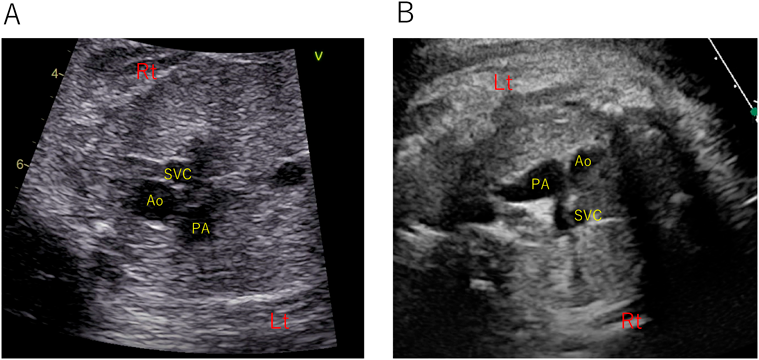

3-vessel viewにおける3血管の並びは非常に重要な情報で,ファロー四徴症(Fig. 3A)では,大動脈が肺動脈–上大静脈を結んだ線よりもやや前方へ位置し,肺動脈は大動脈よりも径が細い.完全大血管転位(Fig. 3B)では,大動脈が肺動脈よりも前方に位置する.総動脈幹症,極型ファロー四徴症,左心低形成では,このviewで2本の血管しか描出できない.以上のことから3-vessel viewだけでも得られる情報が多いことがわかる.3-vessel-trachea viewは,スクリーニングや診断において有用であることが言われており33),4-chamber viewに組み合わせることで診断率が上がる.このviewでは気管と大動脈弓の位置関係を判断できる.大動脈弓が気管の右側を走行すれば右側大動脈弓である.また,大動脈弓径や動脈管径の計測も可能である.大動脈弓離断では,3-vesselから3-vessel-trachea viewに移動する際に,大動脈弓が追えなくなる.大動脈縮窄症の診断にも重要で,動脈管と合流する部位がisthmusであり,その部位での動脈管径との比較が重要である34).さらに,血管輪は3-vessel-trachea viewの最も得意とするところで,右側大動脈弓のU shapeや重複大動脈弓の9 configurationは診断の一助となる35, 36)

Pediatric Cardiology and Cardiac Surgery 37(4): 265-276 (2021)

Fig. 3 Typical abnormal findings of 3-vessel trachea view

A: Tetralogy of Fallot. B: Transposition of the great arteries. Note that PA, Ao, and SVC are not in a straight line. Ao, aorta; PA, pulmonary artery; SVC, superior vena cava.